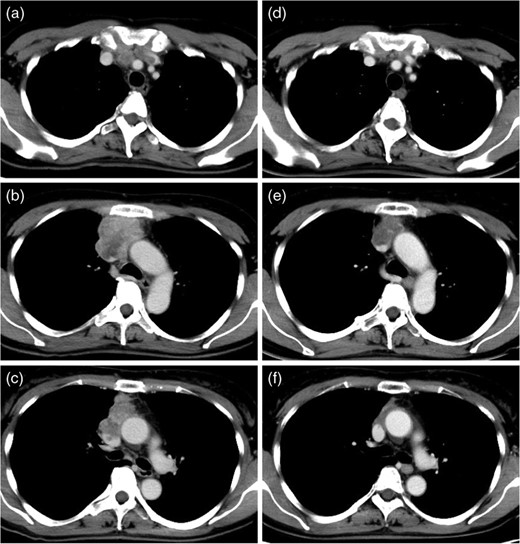

A 61-year-old woman was admitted to our hospital with edema of both upper limbs and face. Blood examination results were almost normal, but, carcinoembryonic antigen was slightly elevated (7.1 ng/ml). A chest X-ray on admission showed an enlarged superior mediastinum and right diaphragmatic elevation (Fig. 1). Enhanced computed tomography (CT) of the chest showed an invasive anterior mediastinal tumor, 6.0 × 3.7 cm in size, invading to bilateral brachiocephalic veins and superior vena cava (SVC) with intraluminal tumor thrombus (Fig. 2a–c). Percutaneous CT-guided biopsy of the tumor was performed immediately after admission, and this tumor was diagnosed as adenocarcinoma, with the suspicion of primary thymic carcinoma or metastatic thymic tumor from gastrointestinal malignancies (Fig. 3a,b). Immunohistochemical examination showed that the tumor cells were positive for cytokeratin 20 and caudal type homeobox 2. Systemic workups revealed no other primary sites or any distant metastases, and she was finally diagnosed as having locally advanced primary thymic adenocarcinoma. Induction CRT was provided to induce a reduction of the tumor with the aim of complete resection. She was administered chemotherapy consisting of carboplatin and paclitaxel on a weekly basis and was treated concurrently with thoracic radiotherapy (50 Gy; 2.0 Gy × 25 fractions). The chest CT after induction CRT demonstrated a reduction of the tumor (partial response: 43% reduction in tumor diameter) and improvement of venous tumor thrombus (Fig. 2d–f). During the CRT, symptomatic SVC syndrome gradually improved, and no severe acute toxicity was observed.

Preoperative enhanced CT of the chest (a, b, c) showed an invasive anterior mediastinal tumor, extending to bilateral brachiocephalic veins and SVC with intraluminal tumor thrombus. After induction CRT, the mediastinal tumor was shrunk and intraluminal tumor thrombus of great veins was improved (d, e, f).